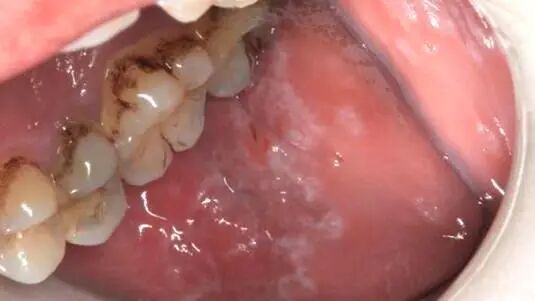

▶ 多在口腔颊黏膜、舌头上出现,像树枝状或网状的白色细纹,有的可能伴随轻微发红;如果长在舌头上,可能会让舌头表面的小突起(舌乳头)变少,舌头活动不灵活,说话、吞咽时有点疼。

▶ 要注意糜烂型、萎缩型、斑块型这三种,相对更容易癌变。

▶ 该咋办:如果只是偶尔看到白纹,没疼没麻,先别慌;但要是出现不明原因的疼痛、麻木,或白纹范围变大,及时去口腔黏膜科查一查。规范调理后,大多能控制住,不会影响生活。